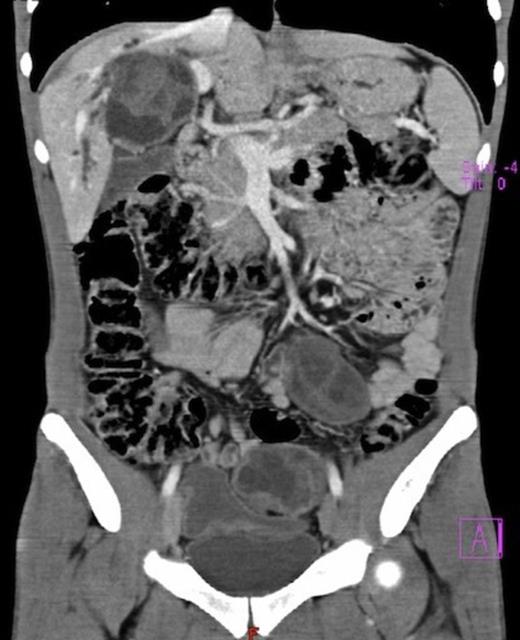

Laboratory investigations showed a slight anaemia, elevation of serum bilirrubin (conjugated 10.6 mg/dl), alkaline phosphatase (959 U/L), gamma-glutamyl transpeptidase (755 U/L). Hydatid serology was positive. Abdominal ultrasound demonstrated multiple cystic lesions spread in the liver, splenic hilum and peritoneal cavity. CT-scan confirmed the presence of numerous hydatid cysts, in different stages of development (type I-IV of Gharbi Classification), ranging from 3 to 8 cm in diameter, with 3 involving the right lobe of the liver and segment 4 (Fig.1). The splenic hilum contained a 4 cm cyst, and 9 more cysts were described in peritoneal cavity: near the gallbladder, in the root of the mesentery, in the right iliac fossa and in the Douglas pouch (Fig. 2). Cholangio pancreatography (MRCP) showed intra-hepatic bile ducts dilatation. Cholangiography (ERCP) was attempted without success. Pre-operative albendazole therapy (10 mg/Kg) was prescribed for 4 weeks.